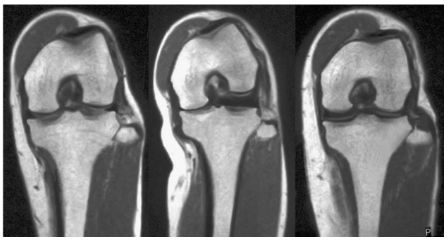

More than 25 years ago Rich Berger performed the first CT evaluation of a painful, not well functioning TKA which showed normal frontal and sagittal radiographs. Based on this experience he published the basics for the axial plane analysis for painful TKA using CT imaging technique [4]. This was followed by the classical paper on the clinical relevance of malrotated components in TKA evaluated with his CT evaluation protocol [5] (Fig 1).

Without knowing all the details of this complex 3-D biomechanics of the patellofemoral joint, Insall has recommended to realign the prosthesis to the extensor mechanism during TKA surgery already 40 years ago. He introduced the tibia tubercle axis (TTA) for rotational alignment (Fig 21) which brings the TT under the trochlea from extension until deep flexion in all cases [1]. Most surgeons follow this simple technique but never thought about the wide variation of the TT to the proximal tibia anatomy. During the last decade several studies using 3-D imaging have shown that proximal tibia axial deformity is common in TKA patients and the TT position to the proximal tibia anatomy is very variable [22,30,48]--. Furthermore, it could be demonstrated that in varus knees external torsional deformities showed a clear correlation to the severity of the frontal malalignment [52]. The most commonly used measurement technique for knees with TKA is the anterior tibia tubercle angle (ATTA), which measures the angle between two lines (Fig 1 B and C) [4,30].